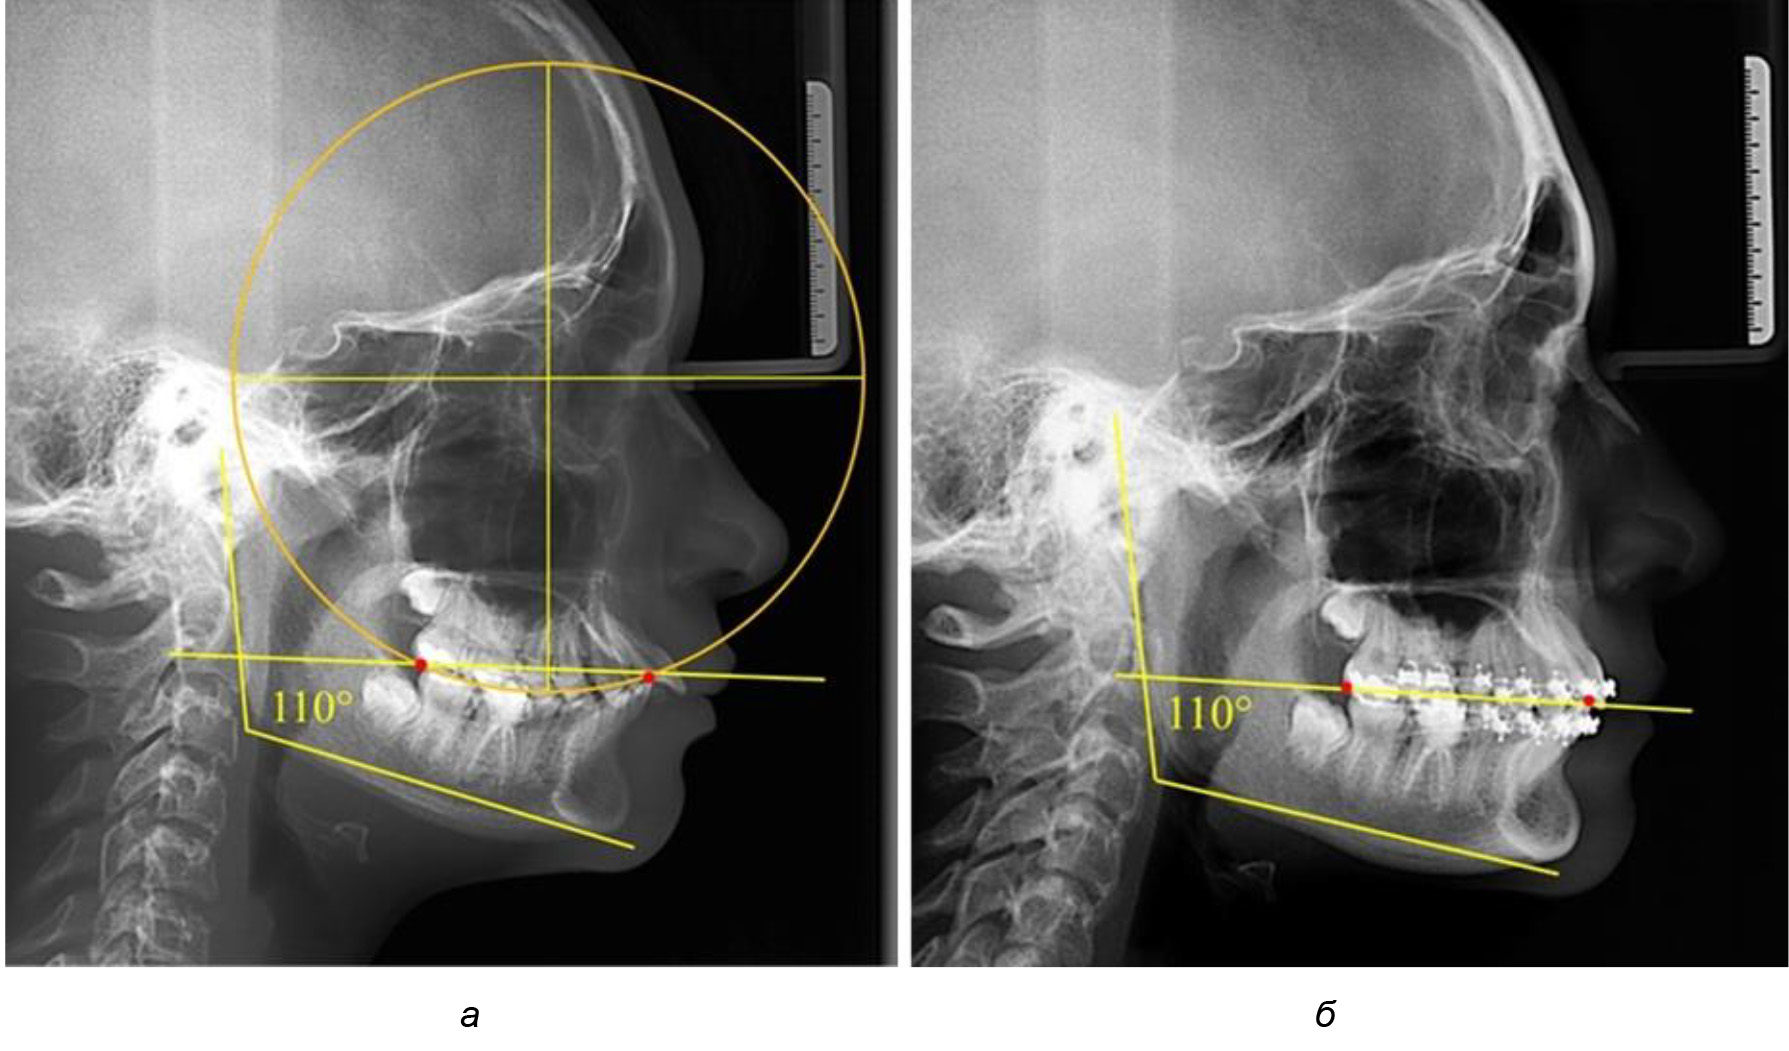

Деление величины радиуса круга к длине окклюзионной линии составило 1,623 ± 0,02. Таким образом, для определения радиуса окружности, соответствующей кривизне окклюзионного контура боковой ТРГ, необходимо измерить расстояние между передней и задней окклюзионными точками и последующим умножением полученной величины на число Фибоначчи (рис. 2).

Рис. 2. Особенности кривой Spee на ТРГ (а) и ОПТГ (б) у людей с признаками вертикального роста